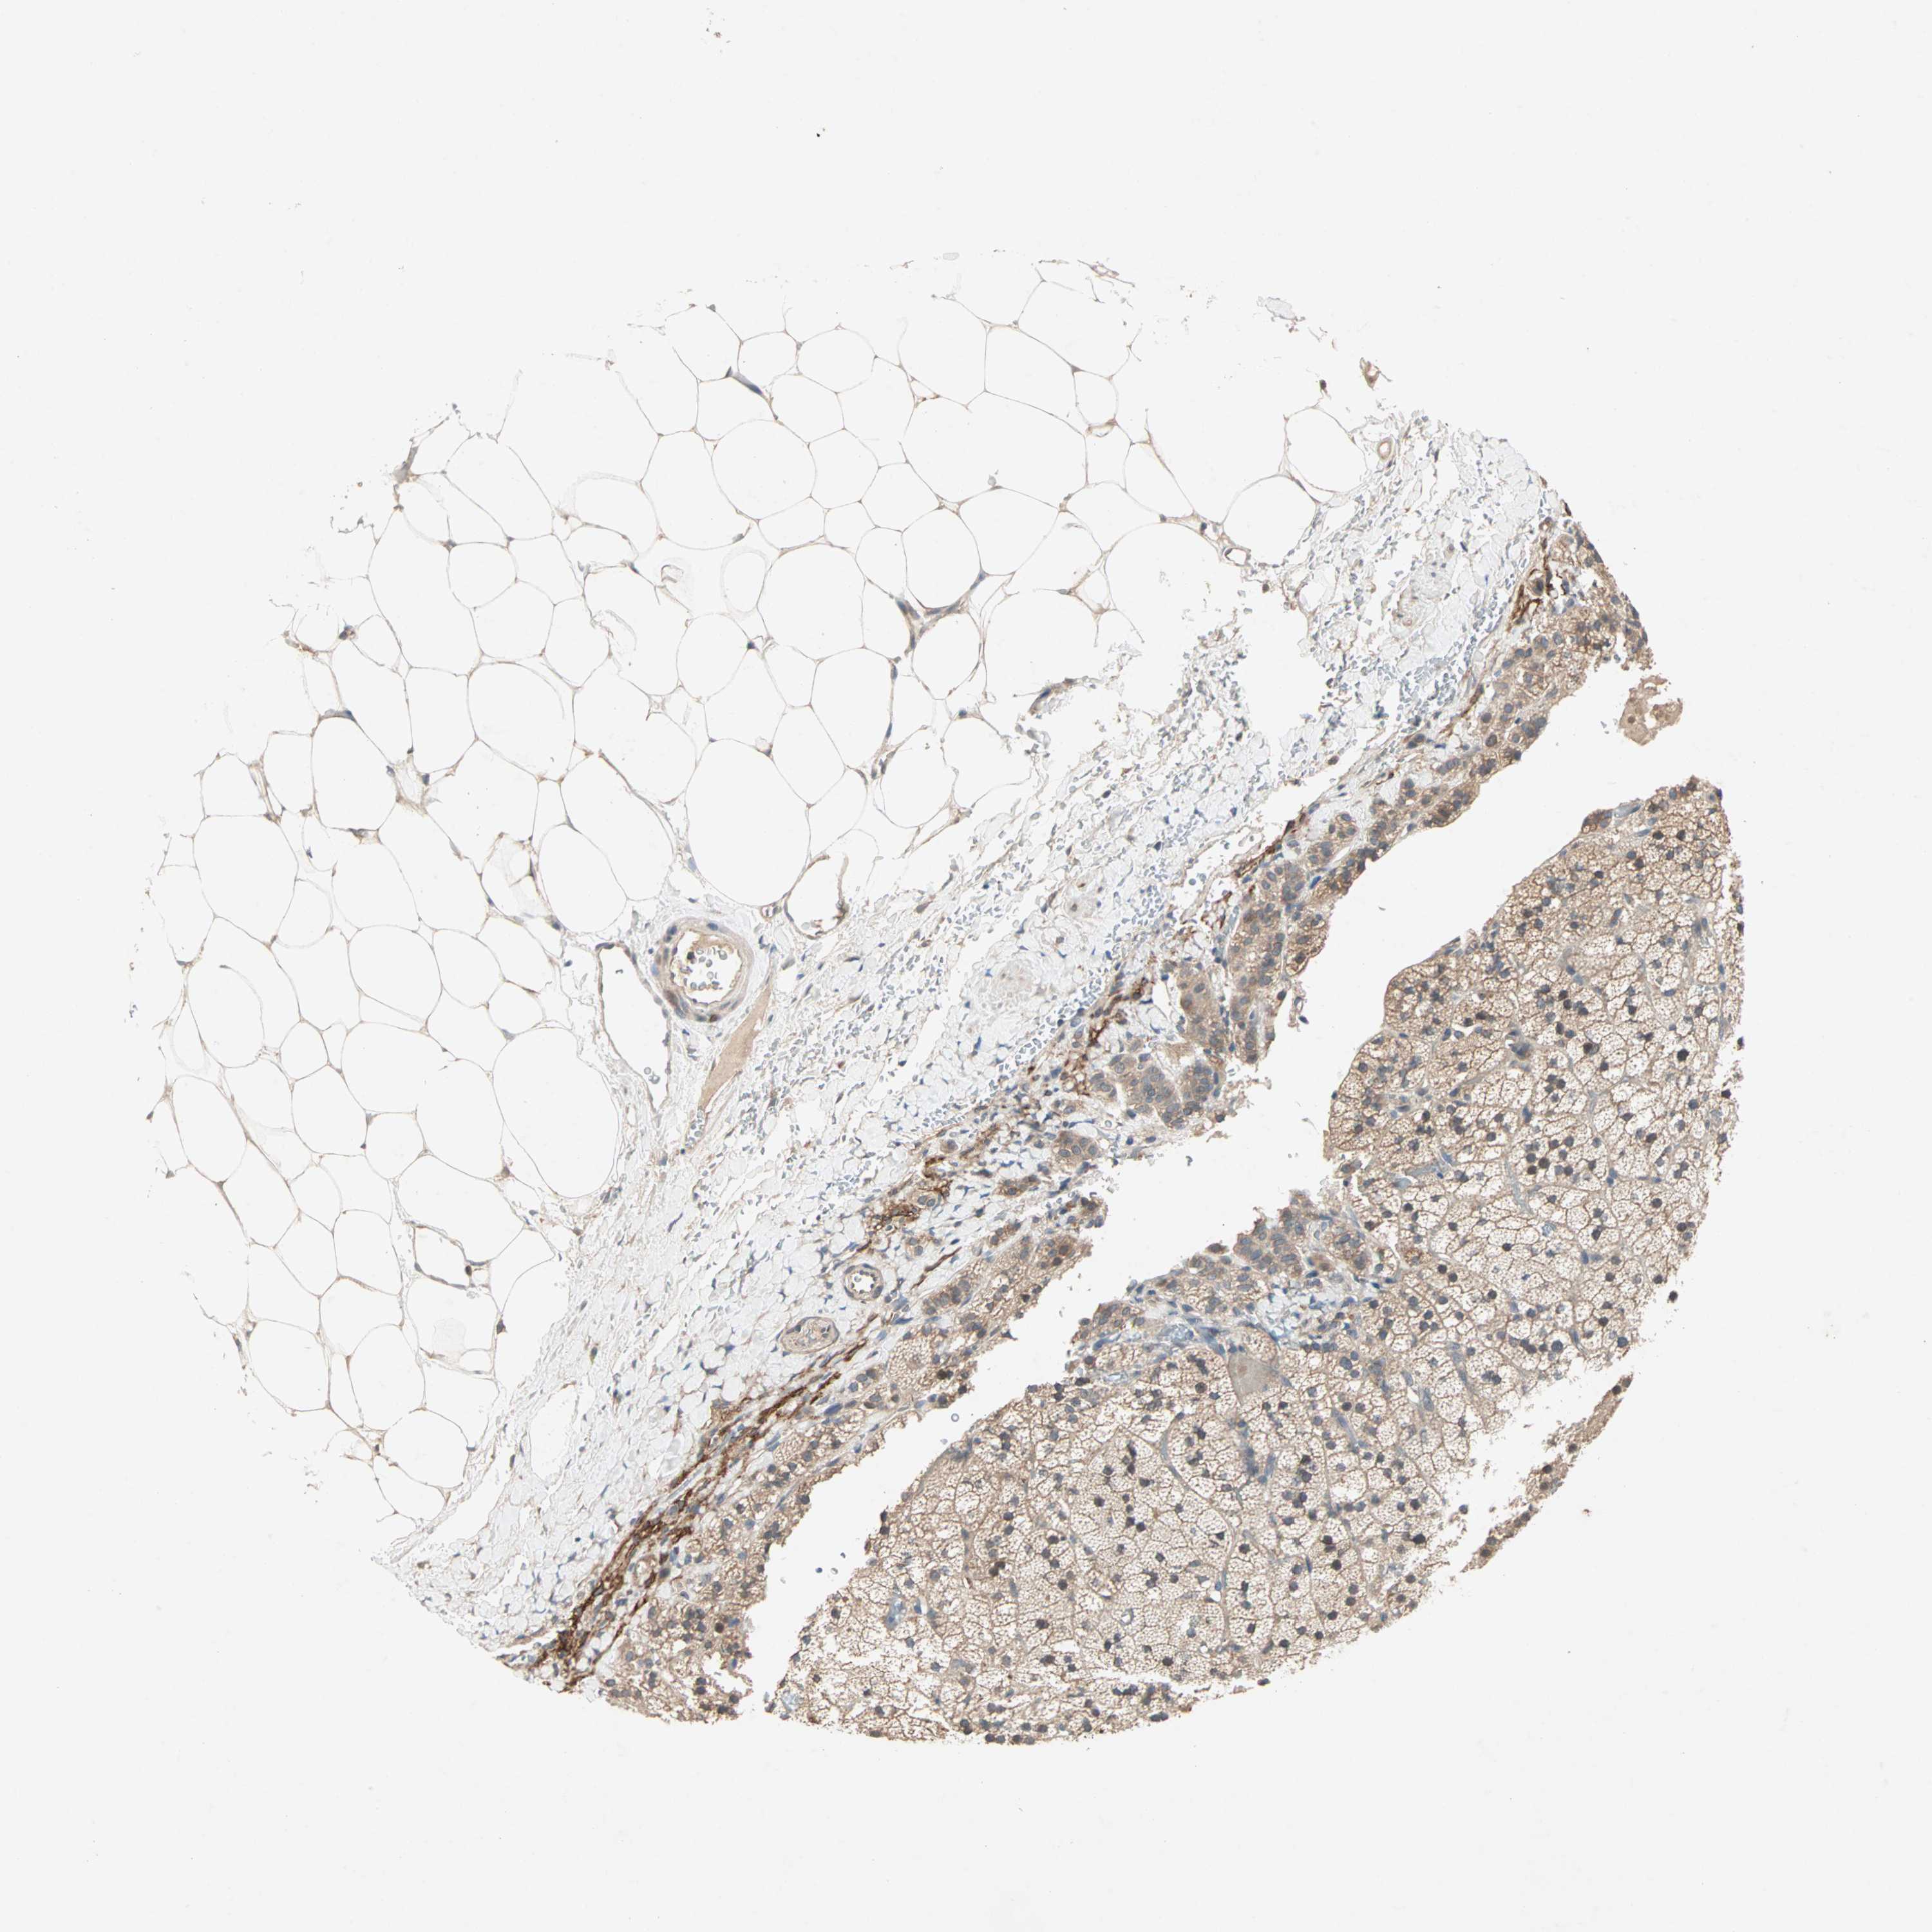

ADRENAL GLAND - Antibody stainingi

Antibody staining in the annotated cell types in the current human tissue is reported as not detected, low, medium, or high, based on conventional immunohistochemistry profiling in selected tissues. This score is based on the combination of the staining intensity and fraction of stained cells.

Each image is clickable and will lead to virtual microscopy that enables deeper exploration of all samples and also displays staining intensity scores, fraction scores and subcellular localization as well as patient and tissue information for each sample.

Antibody HPA005776

Glandular cells Medium